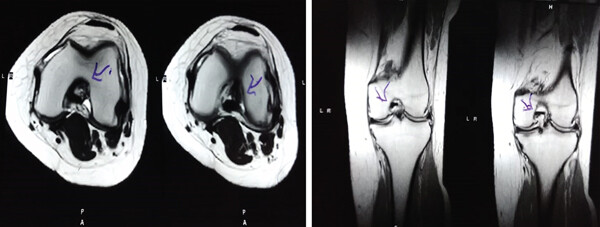

MRI檢查發現半月板損傷處修復:3D MRI 顯示 2 年時半月板撕裂難以辨別。

結論:滑膜間充質干細胞移植后,2年的隨訪中,患者的關節功能改善,MRI檢查發現半月板損傷處恢復,沒有發生導致研究終止的重大不良事件。可以達到干細胞治療半月板損傷長期療效的目標。

影像學檢查:4例MM皮瓣撕裂患者在治療前后交界區中央區域出現缺損,但其中2例患者該區域完全恢復穩定光滑狀態,另2例患者該區域部分恢復。治療前后交界區中央區域皮瓣撕裂的關節鏡評分為0.3±0.5,治療后為4.3±2.1,治療后評分顯著升高。2例患者原有放射狀MM撕裂在治療一年后愈合。

結論:間充質干細胞移植后,隨訪24個月內,患者影像學和關節功能顯著改善,未發生嚴重不良事件。可以達到干細胞治療半月板損傷長期療效的目標。